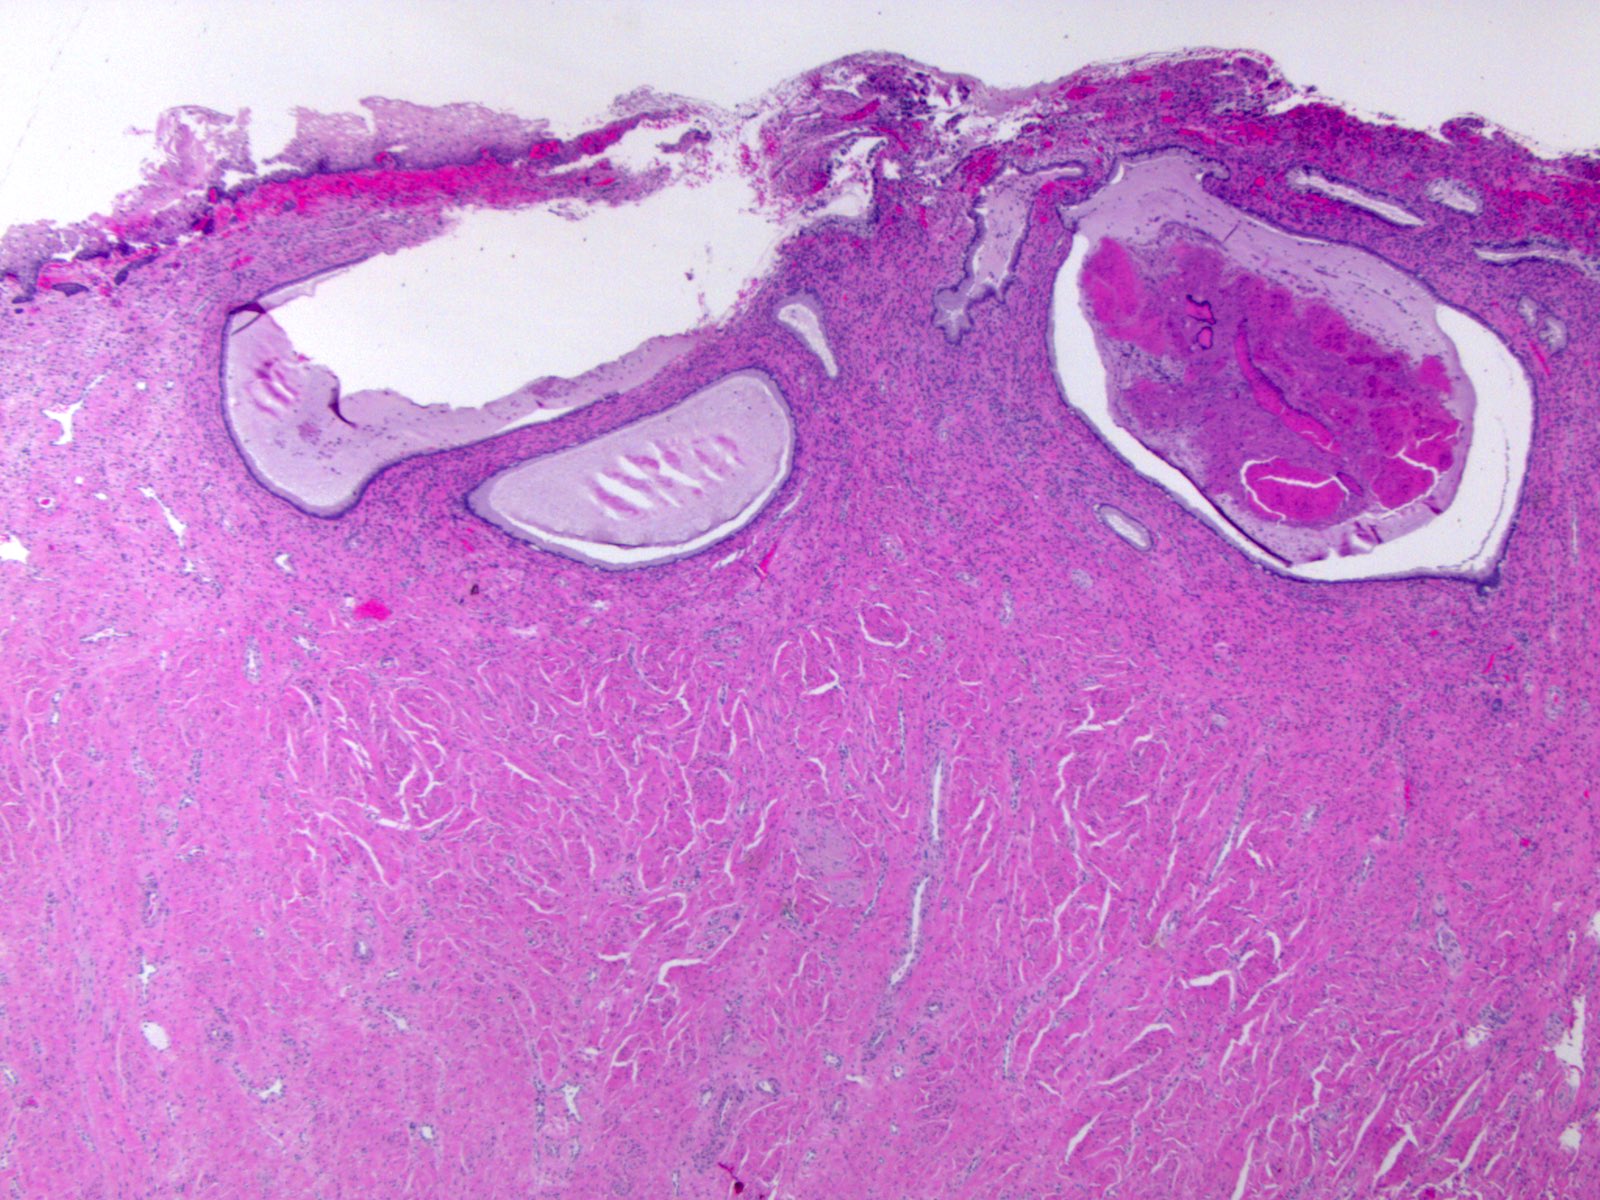

Pathology Outlines Nabothian cysts